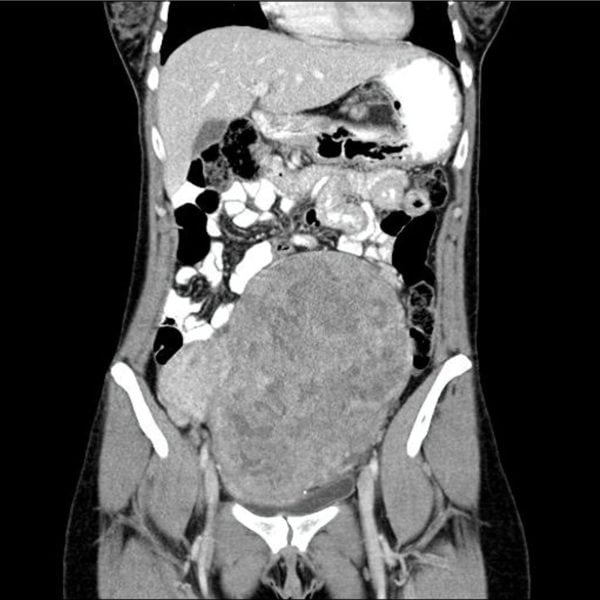

CT/MRI

Myomas are sometimes discovered as an incidental finding when a CT or an MRI has been performed for other reasons. Because of the better tissue specificity and the lack of radiation exposure, an MRI should only be performed if necessary.